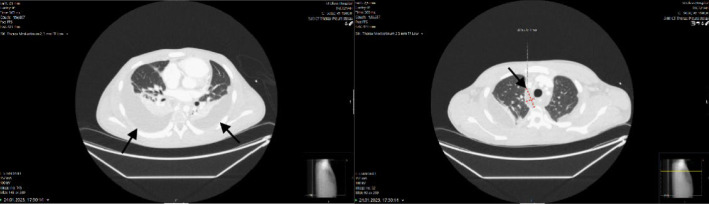

A male in early adolescence presented with 1 week of chest pain, respiratory symptoms and diarrhoea. Thoracic computed tomography (CT) revealed suspicious findings of necrotising mediastinitis without signs of a descending infection. The patient underwent bilateral thoracotomy and laparotomy with several revisions. After 58 days in the hospital, the patient was discharged home, fully recovered, with no sequelae. This case highlights the importance of a multidisciplinary approach when managing severe and rare conditions, emphasising the need for early diagnosis and prompt, appropriate surgical treatment.